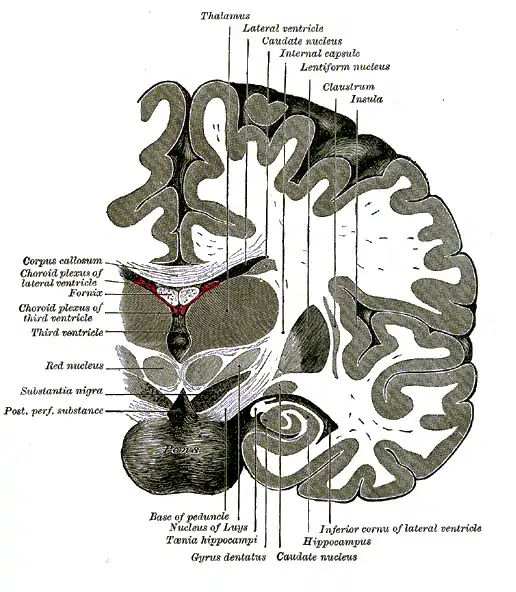

- Neuroanatomy

- The cortex and thalamus

- The Role of the Thalamus